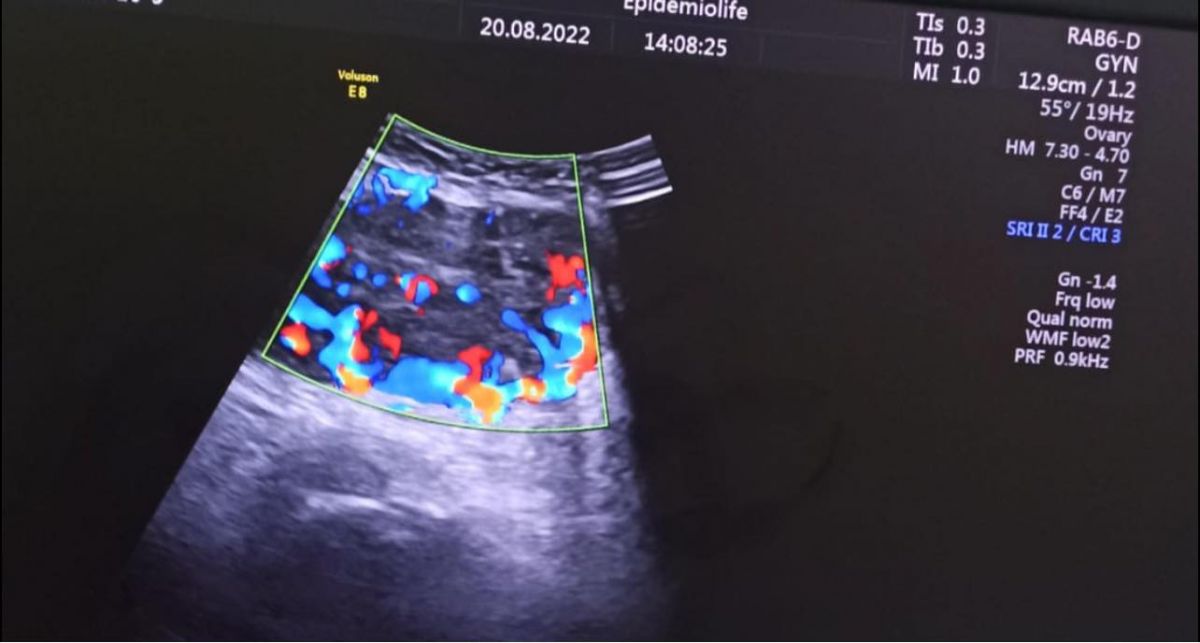

”Ecografic am depistat o formațiune chistica cu multe septuri la nivelul ovarului drept, de aproximativ 20 cm, cu prezență de lichid liber în burtă și o altă formațiune cu caracter solid și vascularizație intensă localizată subcutanat la nivel suprapubian, de aproximativ 7 cm”,

Dr. Alexandra Ciobanu